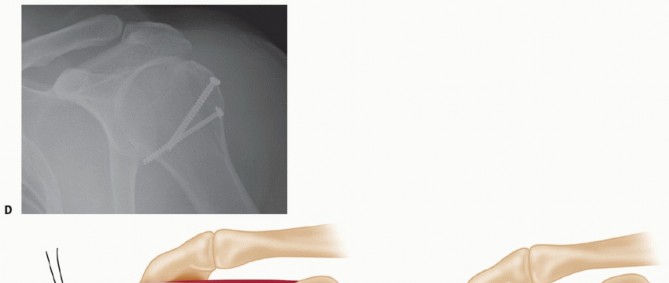

TECH FIG 5 • A. K-wires through drill sleeves are used to maintain plate fixation. Note the position of the superior aspect of the plate in relation to the top of the tuberosity. B. Once the head is secured to the plate, distal screws may be placed. C. Final plate fixation. D. Fluoroscopic image showing screw placement.